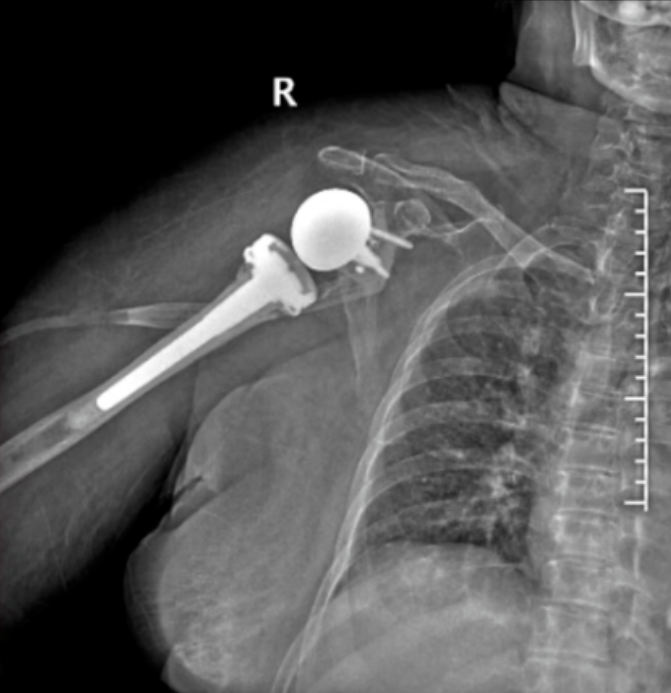

家住高桥的倪奶奶今年76岁,4个月前走路时不慎摔倒,当即感觉右肩剧烈疼痛,右手活动不便。但倪奶奶从小害怕看医生,想着应该只是简单摔伤,过几天自己会好。没想到几天后,手臂开始肿胀,倪奶奶又想起老话常讲伤筋动骨100天,于是决定再忍忍,这一忍就忍了4个月……

浙东骨科医院为倪奶奶手术前